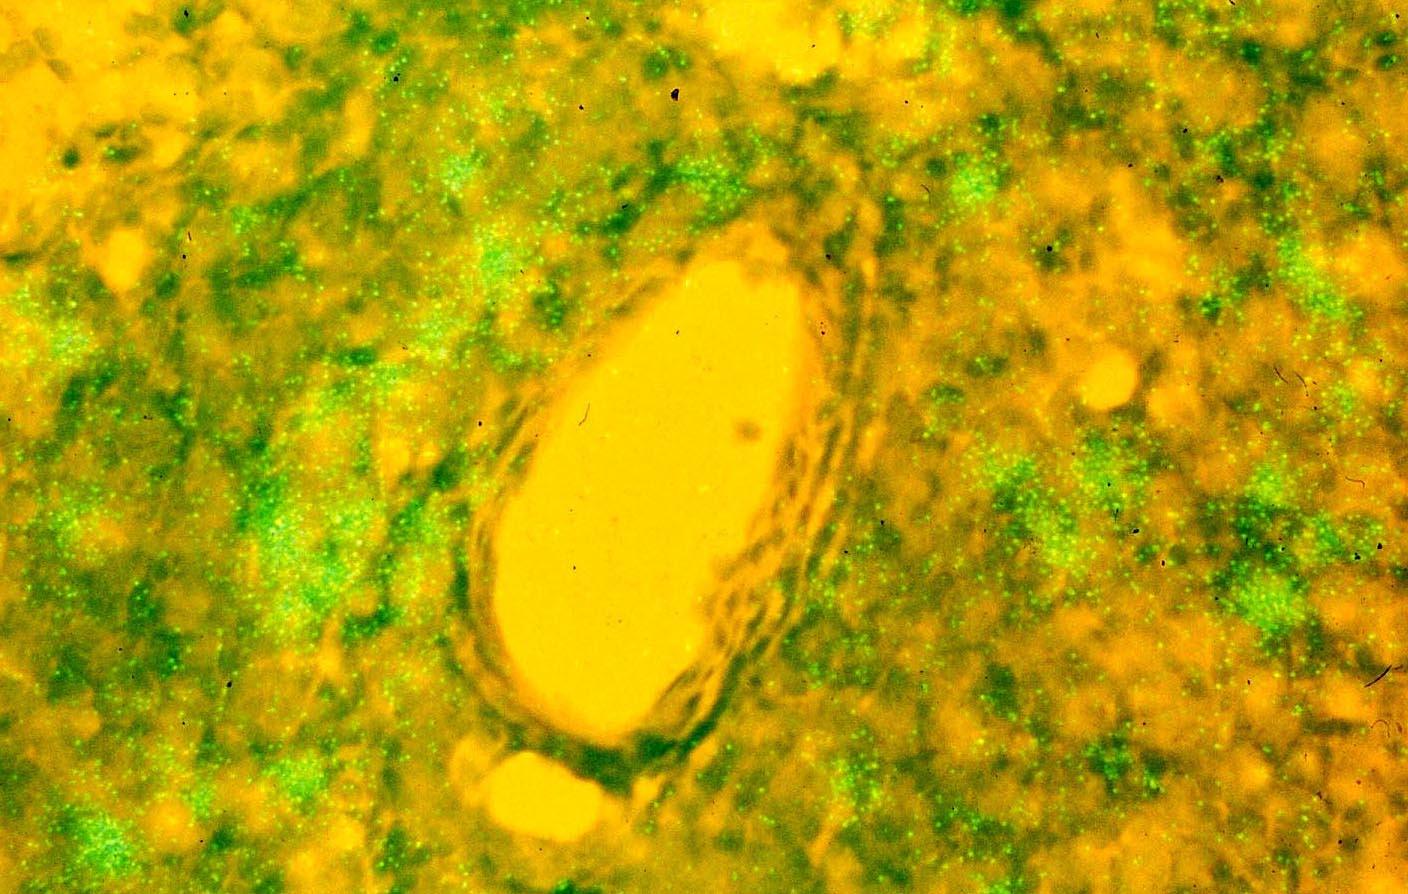

HIV DNA (green nuclei) detected by in situ PCR in CD4+ T cells around a blood vessel

But, where and how to look? The where seemed obvious-most of the then known CD4+ T cell and macrophage targets would be concentrated in lymphoid tissues-and the how to search for 10 attomoles of proviral DNA in single cells became possible with the development of in situ PCR (5). Armed with the technology and lymphoid tissue samples, I was astonished to see one night how many DNA+ cells there were in our lymphoid tissue samples, and could only find the floor’s janitor to share the discovery. We published the story in Nature in back-to back papers with Tony Fauci’s lab (6, 7), both papers confirming earlier work by Paul Racz that the lymphoid tissues were the principal sites of HIV infection (8). We emphasized covert (latent) infection in our paper, while Pantaleo et al. reached the opposite conclusion. HIV infection was always active. This Janus-faced pairing is actually a recurrent theme in lentivirus infections (9) from Visna to HIV-silent infection to hide and persist, and active infection to maintain and spread infection and indirectly cause disease from immunopathological responses to active infection.